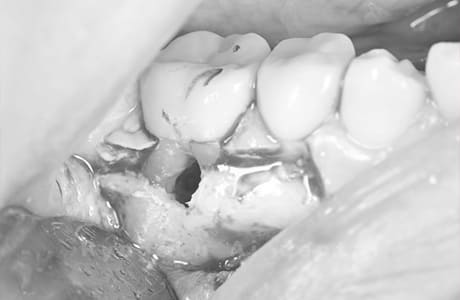

Case05

-

術後2ヶ月

- 原因

- 右下6番近心根パーフォーレーション

- 治療内容

- 外科的パーフォレーションリカバリー治療

- 治療費用

- ¥66,000

右下の奥から2番目の歯に穴が空いており、腫れが引かず、他院で抜歯と診断された患者様です。被せ物を外さずに、穴が空いている部分に外科的にアクセスし、その部分を修復手術を行いました。治療後も再発せず、経過良好です。

<リスク・副作用>

手術後は痛み、腫れ、痺れ、青あざなどの副作用が生じます。痛みは痛み止めを処方しますが、腫れ、青あざは1週間程度生じる場合があります。また、部位によっては神経の走行が複雑で、痺れが残り、長期的にお薬を処方する場合があります。